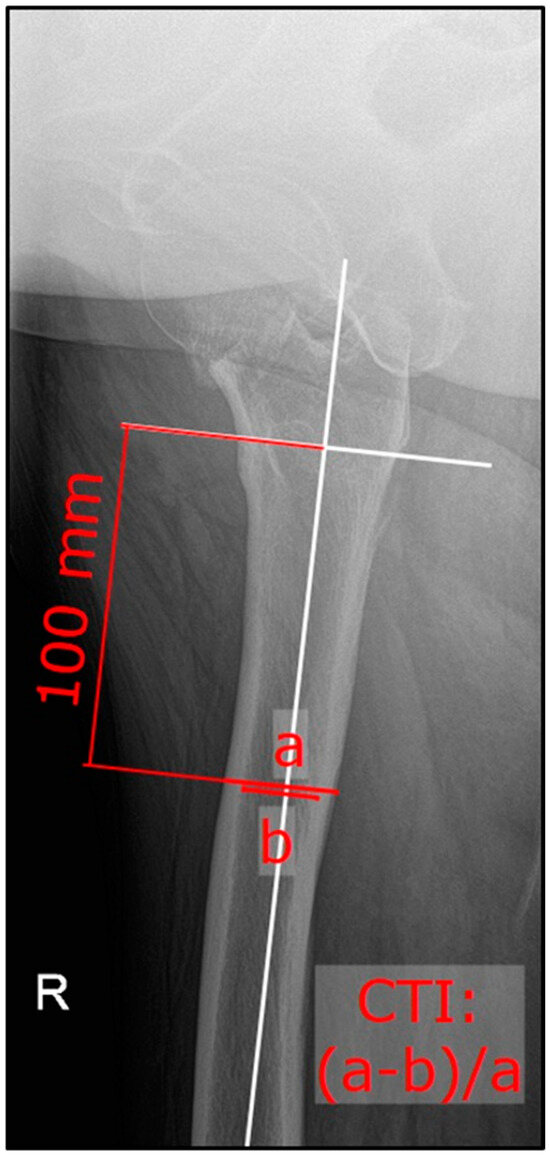

2. Materials and Methods